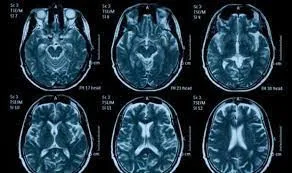

SANTO DOMINGO.- Los primeros signos de autismo en un niño se pueden descubrir antes del nacimiento a través de resonancias magnéticas del cerebro del feto a partir de las 25 semanas de embarazo, indicó un equipo de nerofisiólogos.

Los científicos, para investigar si los escaneos cerebrales hechos previo al nacimiento podrían contribuir a identificar los signos del TEA, analizaron retrospectivamente 39 escáneres cerebrales fetales por resonancia magnética. De ese grupo, nueve de los niños fueron diagnosticados posteriormente con autismo, 20 eran neurotípicos y 10 no tenían TEA pero presentaban otras condiciones de salud que también se observaron en los niños con ese trastorno. Este proceso (escaneos cerebrales) se desarrollaron a media a las 25 semanas de embarazo. Los científicos también usaron un método de etiquetado anatómico automatizado basado en atlas para segmentar los escaneos cerebrales y luego compararon las regiones cerebrales segmentadas entre los diferentes grupos. Las mayores diferencias se encontraron en el lóbulo insular del cerebro, que tenía un volumen significativamente mayor en el grupo de niños con TEA en comparación con los otros tres grupos de control. “La ínsula es una región profunda del cerebro que se cree que desempeña un papel en la conciencia perceptiva, el comportamiento social y la toma de decisiones, entre otras funciones” han explicado. Los resultados obtenidos concordaron con otras investigaciones que han expuesto cambios en la corteza insular en adultos con autismo y sugieren que esas diferencias pueden comenzar en el útero. Asimismo, el grupo de nerofisiólogos también encontraron que los escaneos de los niños afectados con autismo exponían una amígdala y una comisura del hipocampo significativamente más grandes en comparación con los niños que tenían otras condiciones de salud.LO MÁS LEÍDO